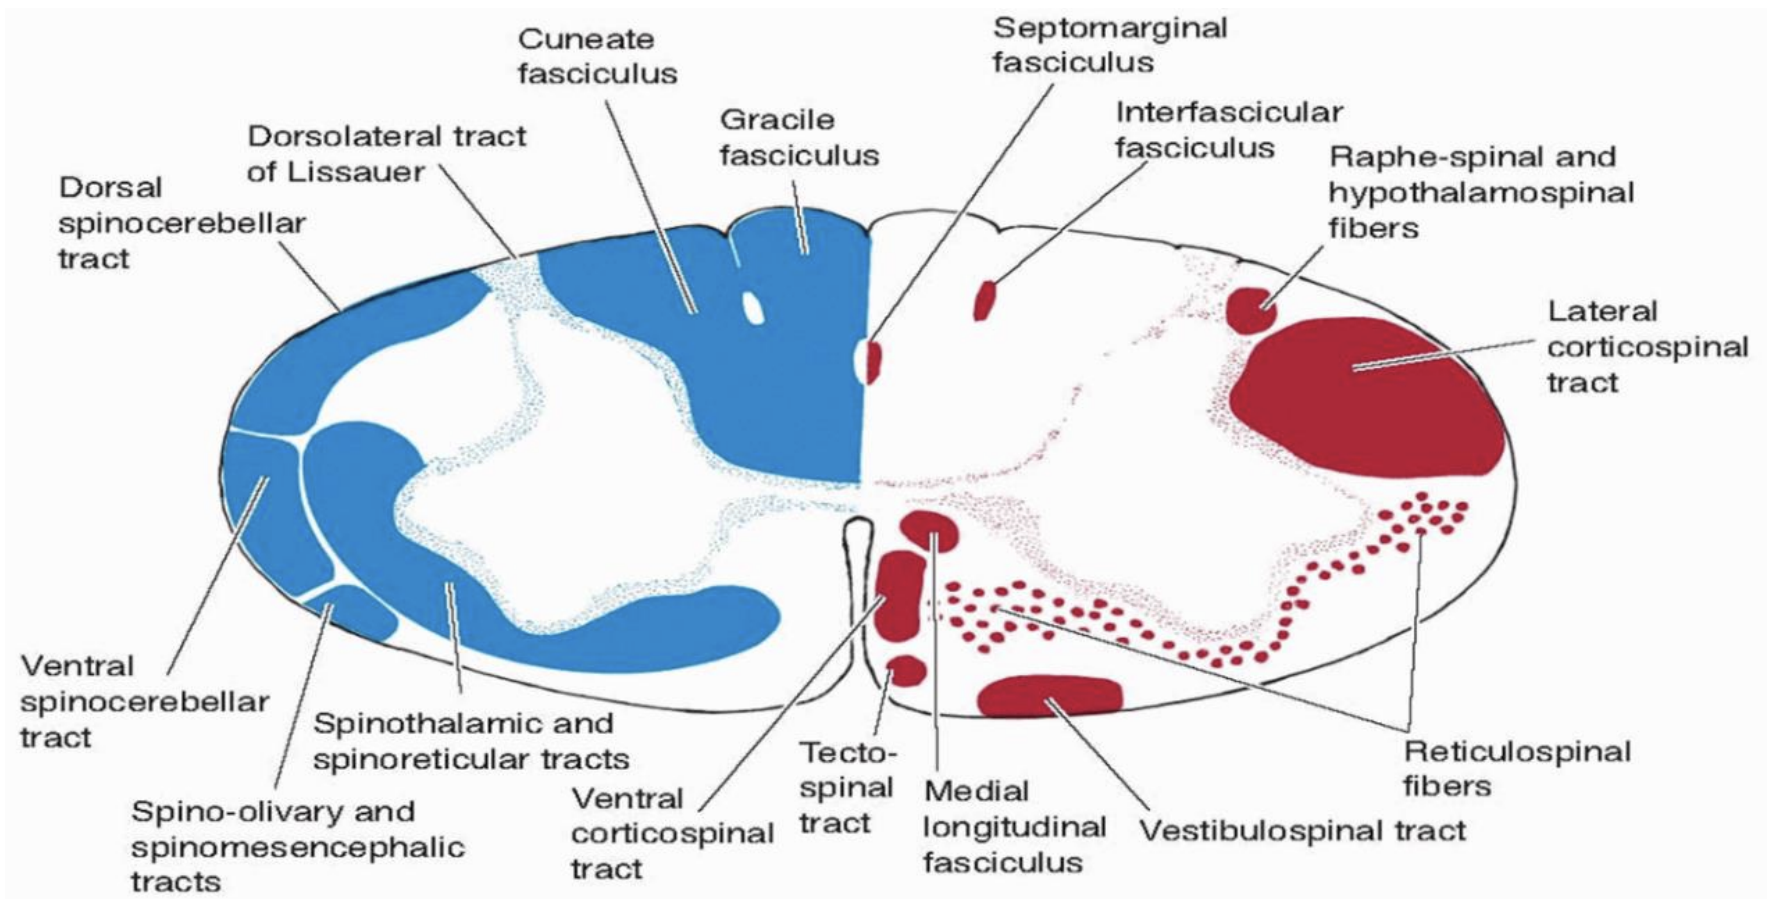

Identify where the different spinal tracts are:

Sensory: posterior columns, anterolateral tracts, spinocerebellar tracts

Motor: ventral and lateral corticospinal tracts, rubrospinal, reticulospinal and vestibulospinal tracts

What is the bell magendie law?

Motor information enters ventrally.

Sensory information enters dorsally.